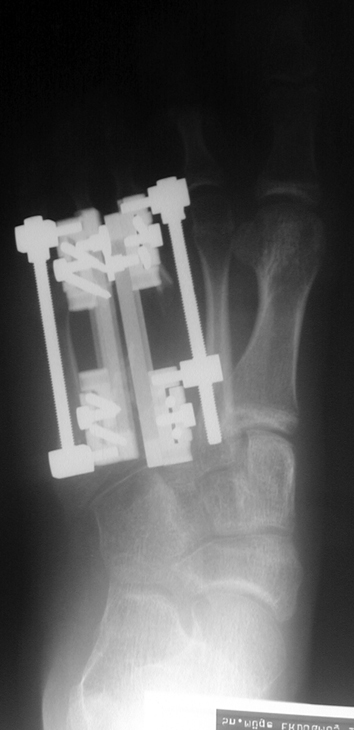

Surgical treatment may be required for metacarpal shortness because of cosmetic disturbance and fatigue in the dominant hand; and for metatarsal shortness because of cosmetic appearance, metatarsalgia, deformity due to dorsal shift of the short finger, pain and pressure ulcers due to plantar shift of the short finger, or difficulty in shoe wearing. Various techniques have been defined for the treatment of congenital metacarpal or metatarsal shortness. However, the most frequently used methods are acute lengthening with grafting, and distraction osteogenesis (callotasis). Callotasis method is preferred for lengthening more than 1 cm. In our department, we prefer distraction osteogenesis with unilateral or circular external fixator for lengthening of metacarpal and metatarsal bones.